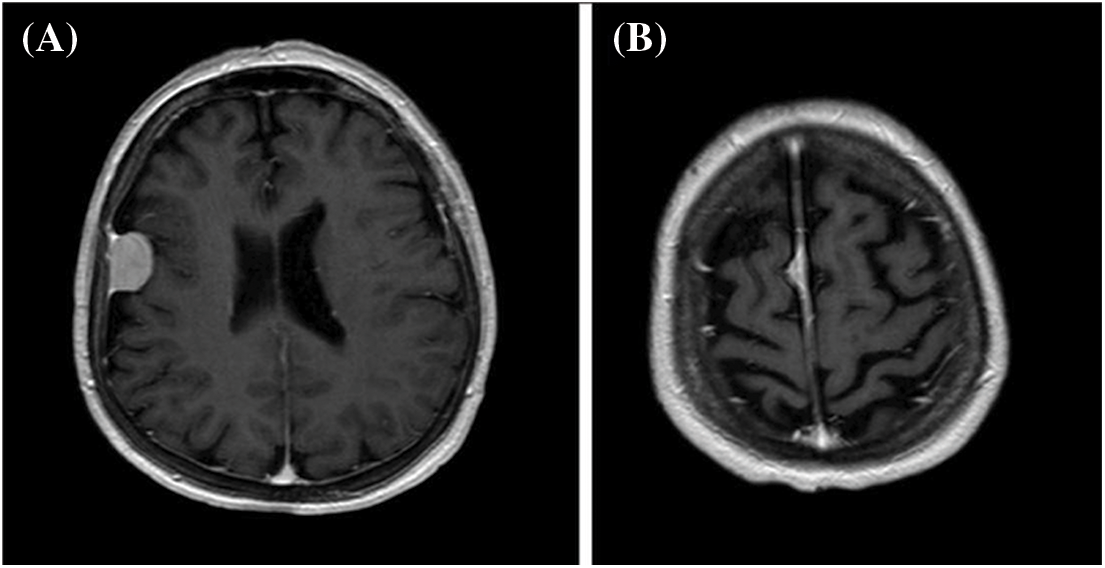

A 60-year-old woman with a history of epilepsy since childhood, arterial hypertension, and incidental diagnosis of meningiomatosis was referred to our department after falling down the stairs. Four years before, the patient had undergone gamma knife treatment of the right frontal convexity meningioma (5.1 cm3) and a smaller falx meningioma (527.1 mm3) (12 Gy-40% and 14 Gy-50%, respectively) (Fig. 1).

Figure 1: Axial post-gadolinium enhancement T1-weighted MR images showing a right frontal convexity meningioma (A) and a right anterior parafalx meningioma (B)